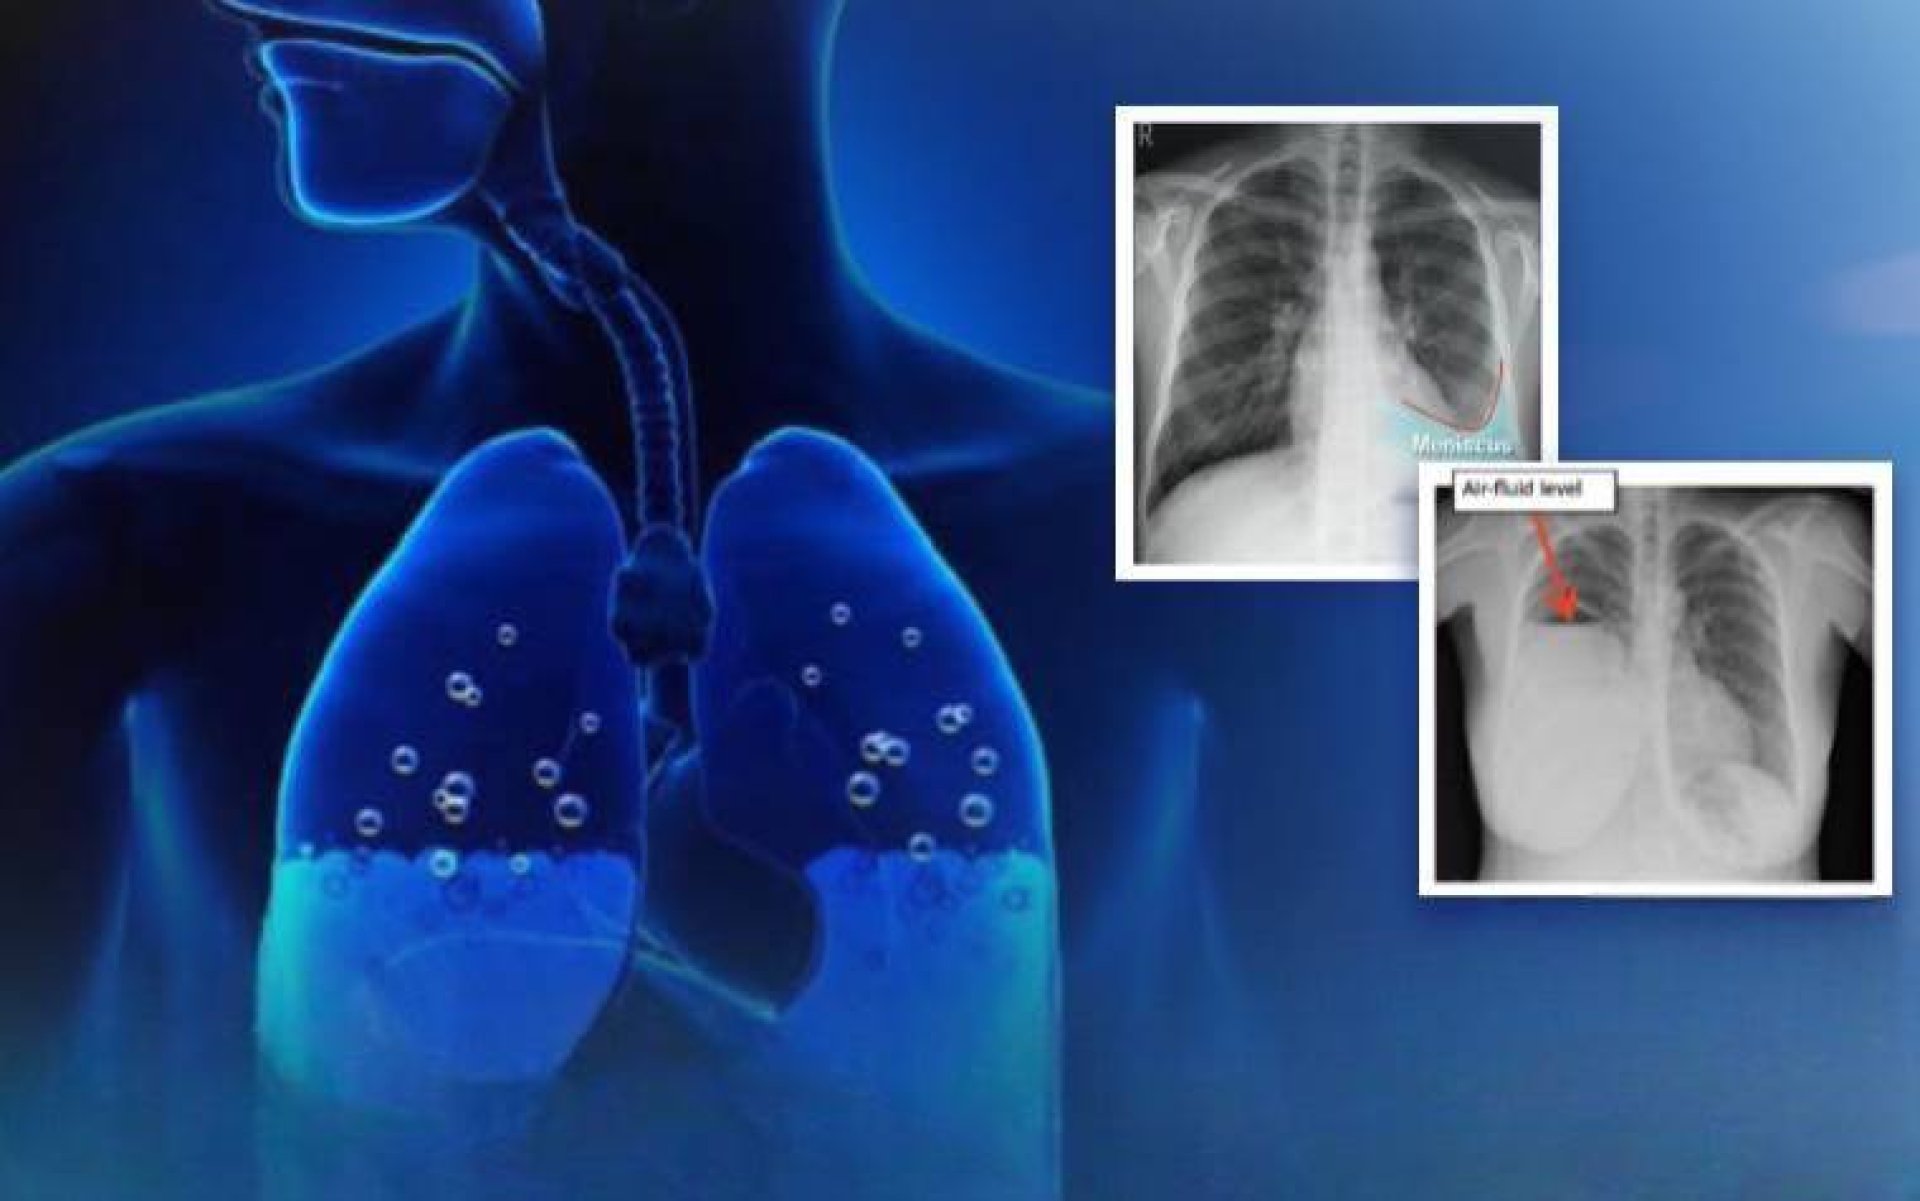

"ภาวะ น้ำในเยื่อหุ้มปอด (Pleural effusion) คือภาวะที่มีของเหลวสะสมอยู่ในช่องเยื่อหุ้มปอด (ระหว่างเยื่อหุ้มปอดชั้นในที่คลุมปอดกับเยื่อหุ้มปอดชั้นนอกที่ติดกับผนังอก) สามารถเกิดได้จากหลายสาเหตุ โดยปกติมักเกิดจาก 2 ประเภทใหญ่ตามลักษณะของสาเหตุที่เกิดขึ้น"

ในกลุ่มที่สองเกิดจากตัวปอดเอง (Exudative Pleural Effusion) ซึ่งมักจะเกิดจากมะเร็ง (เช่น มะเร็งปอด, มะเร็งเต้านมกระจายมาที่เยื่อหุ้มปอด), วัณโรคปอด (Tuberculosis), ปอดติดเชื้อ (Pneumonia) อันเกิดจากเยื่อหุ้มปอดอักเสบหรือมีการอุดตันของระบบน้ำเหลือง รวมถึงของเหลวที่มีโปรตีนสูงและเซลล์อักเสบจำนวนมาก โดยการรักษานั้น หากเกิดจากมะเร็งเราสามารถเอาน้ำออกแล้วใส่ยาเคลือบปอดเพื่อป้องกันการกลับมาเป็นซ้ำได้ (chemical pleurodesis) และในส่วนของกลุ่มที่เกิดภาวะติดเชื้อ เช่น วัณโรคหรือปอดติดเชื้อ หากดำเนินการรักษาแก้อาการของตัวโรค โดยลดอาการบวมน้ำลง อาการก็มักจะดีขึ้นตามมา แต่อาการที่พบในผู้ป่วยอยู่บ่อยครั้ง เช่น มีอาการหายใจลำบาก, มีภาวะเจ็บหน้าอก (โดยเฉพาะเวลาหายใจลึก ๆ) หรือไอแห้ง ๆ มีน้ำเสียงลดลง เหล่านี้แพทย์มักจะวินิจฉัยว่าเกิดจากน้ำในเยื่อหุ้มปอด ซึ่งสามารถใช้การเอกซเรย์ทรวงอก, อัลตราซาวด์ หรือ CT scan และอาจมีการเจาะน้ำในเยื่อหุ้มปอด เพื่อนำไปตรวจหาสาเหตุที่แน่นอน